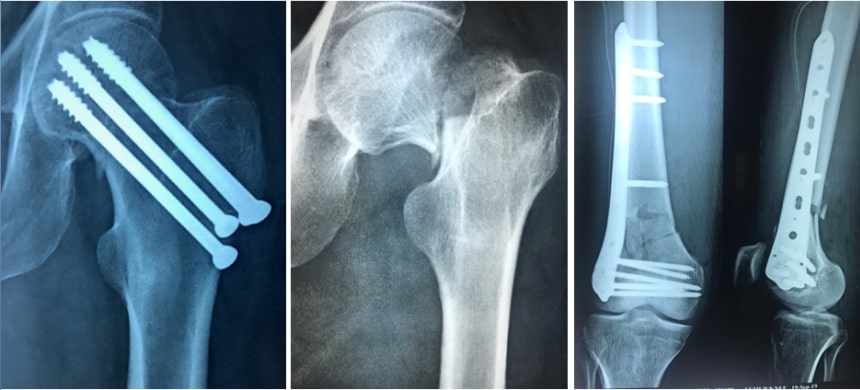

But if the fragments are displaced from each other then there is a lot of chance of non-union of the fracture. So this fracture should be fixed in the correct anatomical position. This kind of fixation needs the use of plates, screws etc. If we fix the fragments in good anatomical position and if the bone fragments get very good blood supply then the fracture will unite very well.

Most of the fractures of the leg bones are operated and fixed using this keyhole surgery. Most of the fractures of arm and forearm are fixed with plate and screws. Intra-articular fractures are the fractures involving the articular surface of bones. They need to be reconstructed properly. They should be fixed with proper implants. This fixation is very important to get back the moments of any joint.

Fixing fractures using metal plates and screws has been in practice for more than 50 years. Most of the times stainless steel has been used to make this kind of plate and screws. Nowadays titanium is being used as a preferred metal for the preparation of plates, screws, nails , locking nails and elastic nails. Both these implants are very good. But titanium has got some advantages over stainless steel. Titanium is not getting rusted and is more bio compatible. Titanium will not interfere with the CT scans. But it is costly comparing with stainless steel.